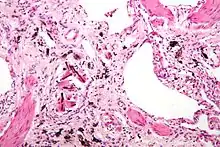

Asbestosis is the scarring of lung tissue (beginning around terminal bronchioles and alveolar ducts and extending into the alveolar walls) resulting from the inhalation of asbestos fibers. There are two types of fibers: amphibole (thin and straight) and serpentine (curly). All forms of asbestos fibers are responsible for human disease as they are able to penetrate deeply into the lungs. When such fibers reach the alveoli (air sacs) in the lung, where oxygen is transferred into the blood, the foreign bodies (asbestos fibers) cause the activation of the lungs' local immune system and provoke an inflammatory reaction dominated by lung macrophages that respond to chemotactic factors activated by the fibers.[21] This inflammatory reaction can be described as chronic rather than acute, with a slow ongoing progression of the immune system attempting to eliminate the foreign fibers. Macrophages phagocytose (ingest) the fibers and stimulate fibroblasts to deposit connective tissue.

Due to the asbestos fibers' natural resistance to digestion, some macrophages are killed and others release inflammatory chemical signals, attracting further lung macrophages and fibrolastic cells that synthesize fibrous scar tissue, which eventually becomes diffuse and can progress in heavily exposed individuals. This tissue can be seen microscopically soon after exposure in animal models. Some asbestos fibers become layered by an iron-containing proteinaceous material (ferruginous body) in cases of heavy exposure where about 10% of the fibers become coated. Most inhaled asbestos fibers remain uncoated. About 20% of the inhaled fibers are transported by cytoskeletal components of the alveolar epithelium to the interstitial compartment of the lung where they interact with macrophages and mesenchymal cells. The cytokines, transforming growth factor beta and tumor necrosis factor alpha, appear to play major roles in the development of scarring inasmuch as the process can be blocked in animal models by preventing the expression of the growth factors.[22][23] The result is fibrosis in the interstitial space, thus asbestosis.

Extensive fibrosis of pleura and lung parenchyma.